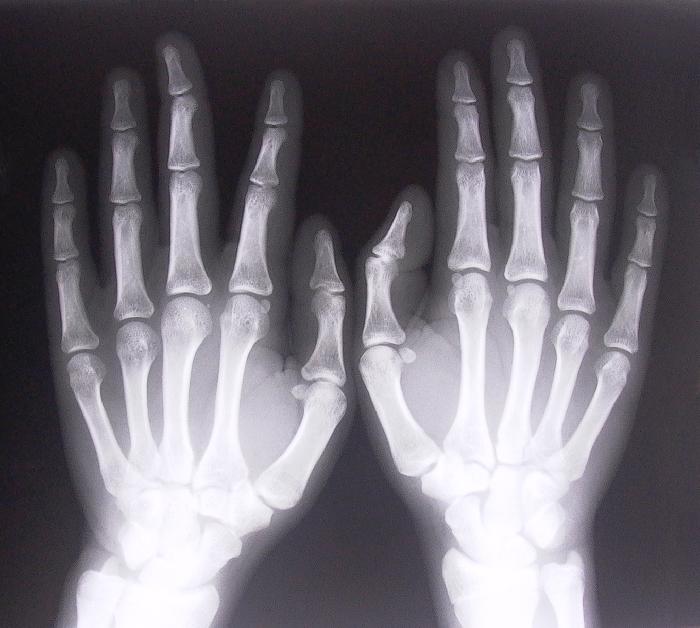

El más visible y principal síntoma de la artritis reumatoide es la inflamación de las articulaciones y el consecuente dolor. Las más afectadas por esta patología son:

• las muñecas

• dedos de manos y pies

La inflamación puede dar lugar a la deformación de las articulaciones, sobre todo cuando la enfermedad está en un estadio avanzado. Y es que el daño en la membrana sinovial hace que los huesos puedan cambiar de posición y se produzca la deformidad.